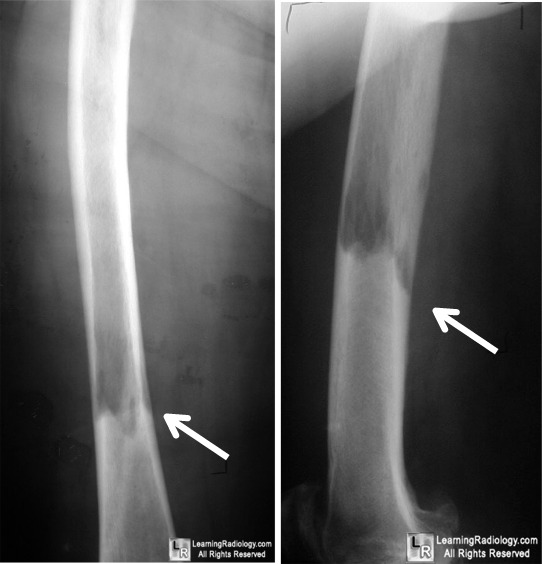

From www.learningradiology.com

LearningRadiology Paget's Disease Lytic Lesions  Paget’s disease of bone (pdb) is a benign disorder of bone characterised by focal areas of disorganised bone turnover in a single bone (monostotic pdb) or multiple bones (polyostotic. This process gives rise to osteoblasts from the. Paget disease of the bone occurs with an increase in bone resorption, leading to a decrease in bone mass and lytic structures. Early. Paget's Disease Lytic Lesions.